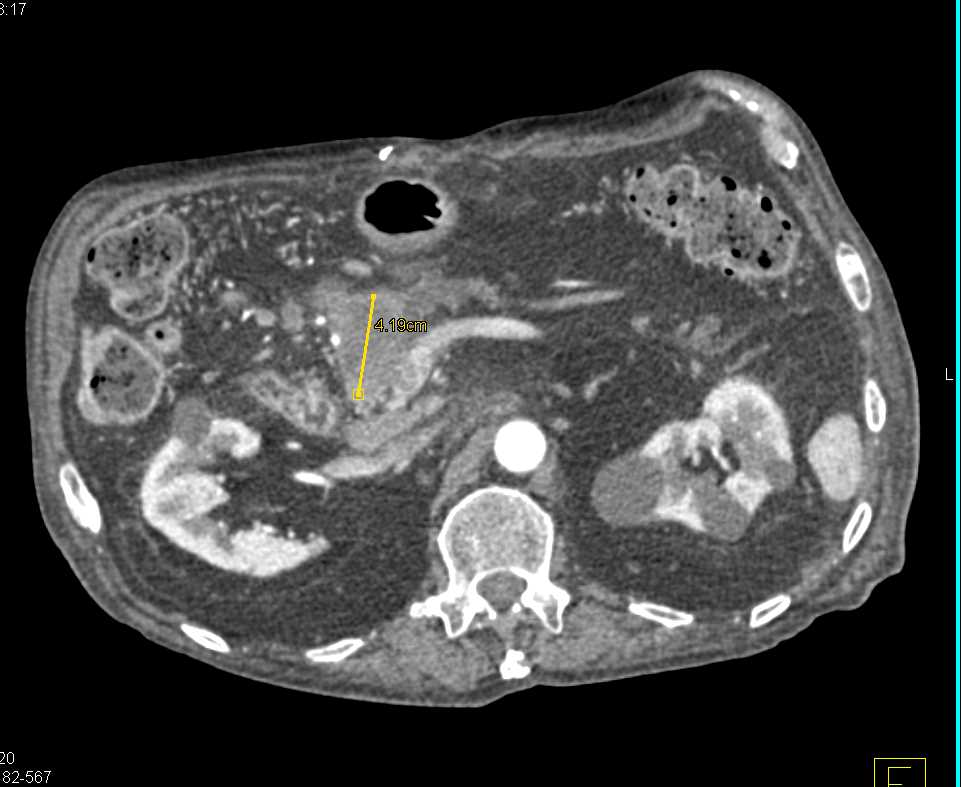

Carcinoma Body of Pancreas with Dilated Pancreatic Duct